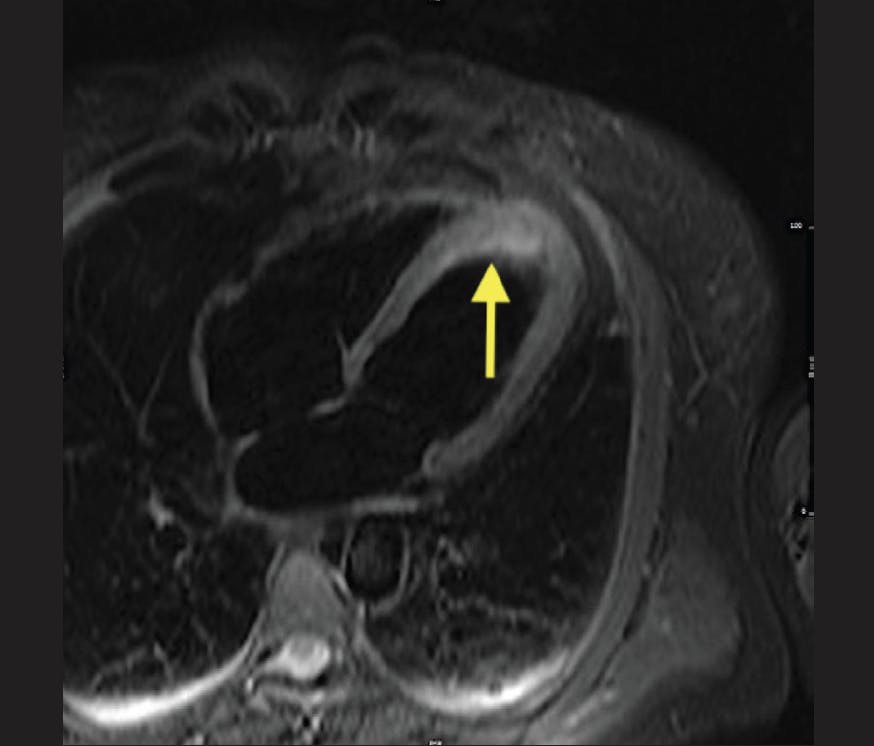

A woman in her mid 40s with no previous history of coronary artery disease, but low-density lipoprotein cholesterol (68 mg/dL) treated with atorvastatin and a 15 pack-year history of smoking, called the emergency medical team at 2:01 pm, 10 minutes after sudden onset of retrosternal chest pain radiating to the left arm. At 2:15 pm, a 12-lead electrocardiogram showed ST-segment elevations in anterior leads V2 to V5. Her blood pressure was 120/80 mm Hg and her heart rate was 95 beats per minute. The attending emergency physician in the ambulance administered 500 mg of acetylsalicylic acid, 5,000 IU of unfractionated heparin, and 10 mg of morphine via intravenous injection. The patient was handled according to the regional “STEMI Fast Track” and directly admitted to the cardiac catheterization laboratory at 2:55 pm. Focused transthoracic echocardiography revealed impaired LV function with anterior hypokinesia and an LVEF of 44%. The first angiogram, obtained at 3:05 pm, showed a proximally occluded left anterior descending artery that was successfully crossed with a guidewire at 3:28 pm (door-to-wire, 34 minutes) and three drug-eluting stents were implanted due to significant sequential coronary stenoses. SSO2 therapy was initiated by upgrading the femoral access to a 7-F sheath at 4:30 pm for withdrawal of arterial blood and positioning of a 5-F JL4 catheter within the ostium of the left main coronary artery for infusion of supersaturated blood. Intracoronary SSO2 therapy was applied for 60 minutes without incident. The patient was transferred to the chest-pain unit where a cardiac MRI performed on day 4 revealed that an extensive anteroapical region of the myocardium was at risk as indicated by edema (Figure 1). However, there was only a small region of nontransmural late gadolinium enhancement (Figure 2). The area at risk was calculated at 17 g (23.3% of the myocardium), with the final infarct size of 6.1 g (36% of the risk zone) resulting in a myocardial salvage index of 64%, with observation of 0% MVO. Based on a recent study by Park et al, we would have expected some MVO to be present in this case, and the salvage index in this case was higher than our expectations.13 The final LVEF was 60% by transthoracic echocardiography and 57% by MRI.

Figure 2. Small region of late gadolinium enhancement at day 4.